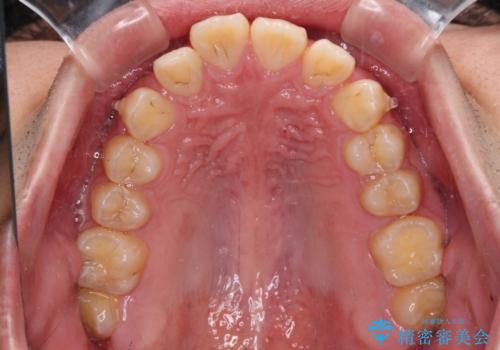

- 深く咬みこんだ前歯と、それに伴い前方に突出した上顎前歯を気にして来院された患者様です。

下顎の歯列は、奥歯が前方に傾斜し、前歯が上顎の歯の付け根に食い込むように内側に傾斜していました。

また、左右の犬歯の位置関係は上顎歯列が前方に位置する咬み合わせとなっており、インビザライン単体で治療するよりは、ワイヤー装置や補助装置を併用した方がより良い仕上がりになることが期待されました。

来院時は学生であったので、補助装置により上顎臼歯を後方に移動させ、下顎歯列はワイヤー装置による傾斜を改善させ、就職のタイミングでインビザラインにて仕上げていくこととしました。